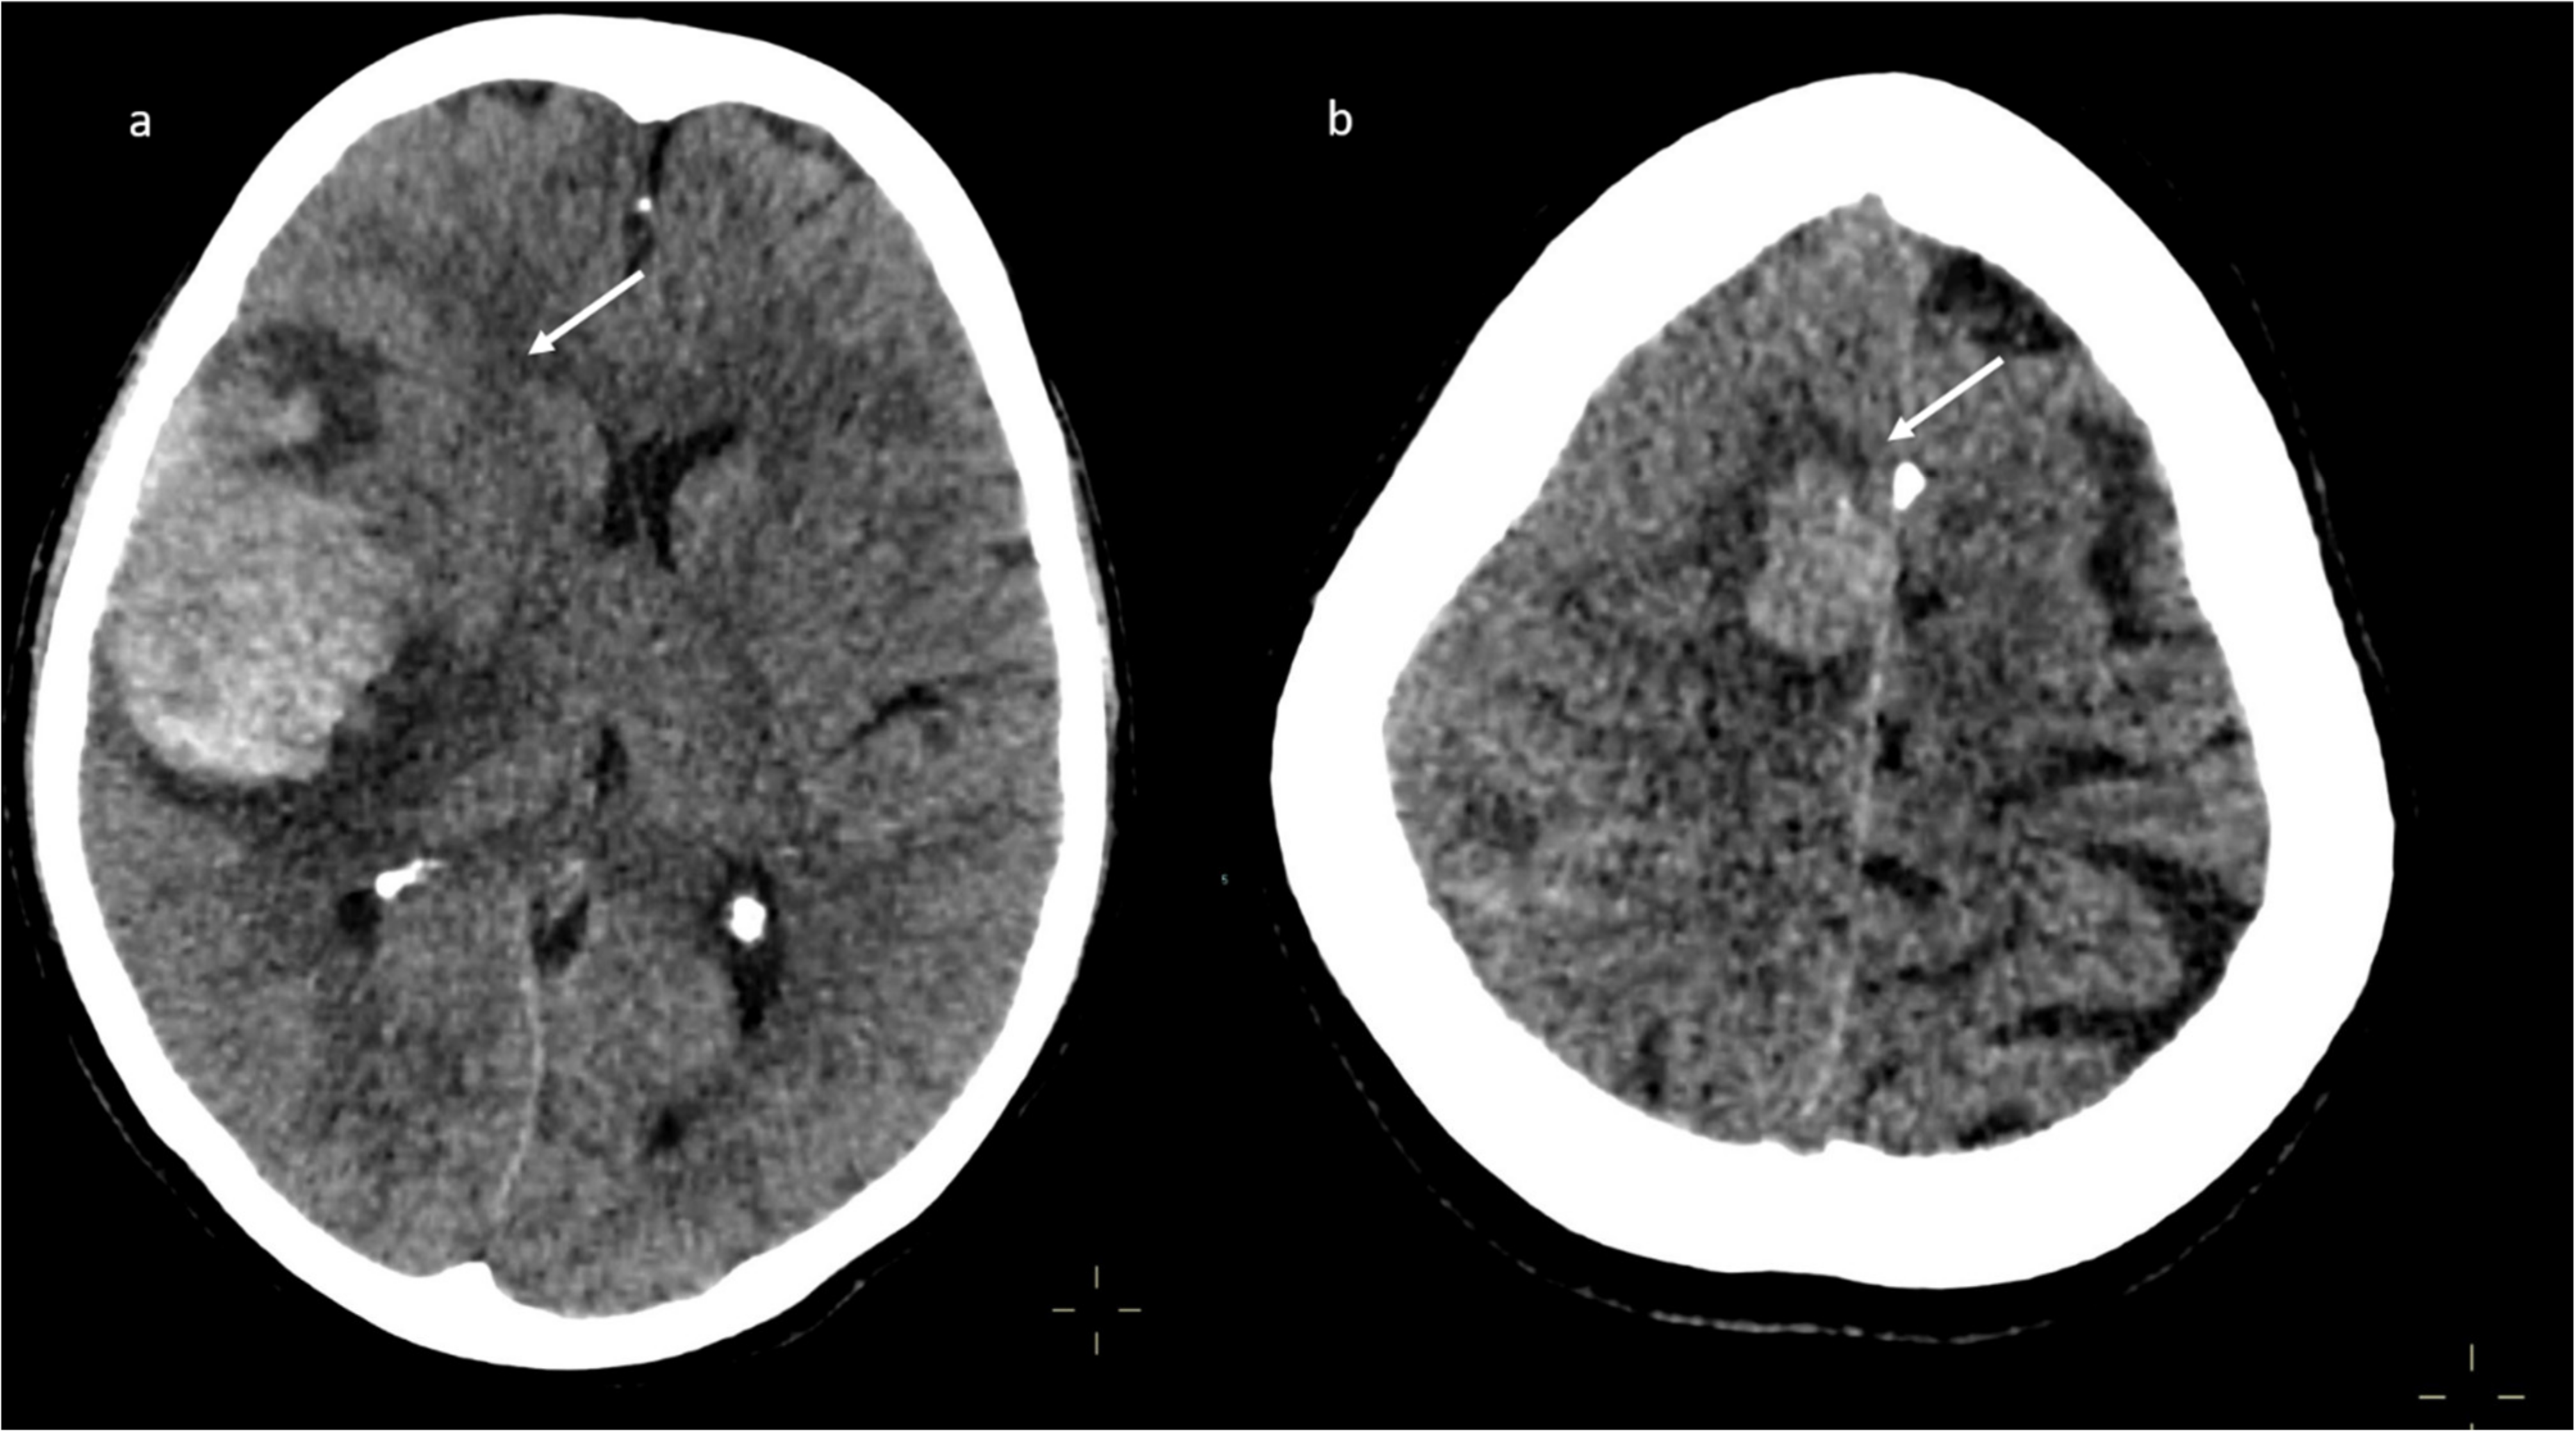

A brain computed tomography (CT) scan showed multiple subacute intra-axial hemorrhages in atypical locations, including the right frontal and the temporal lobes (Figure 1), with ipsilateral hemorrhagic subarachnoid suffusion, raising the suspicion of Labbè/superior longitudinal sinus thrombosis, even if brain angio-CT demonstrated only a non-occlusive thrombosis of the vein of Galen (Figure 2a), but also a floating thrombus within the aortic arch (Figure 2b).

Figure 1.

Brain computed tomography (CT) scan: presence of multiple subacute intra-axial hemorrhages in atypical locations (a,b).